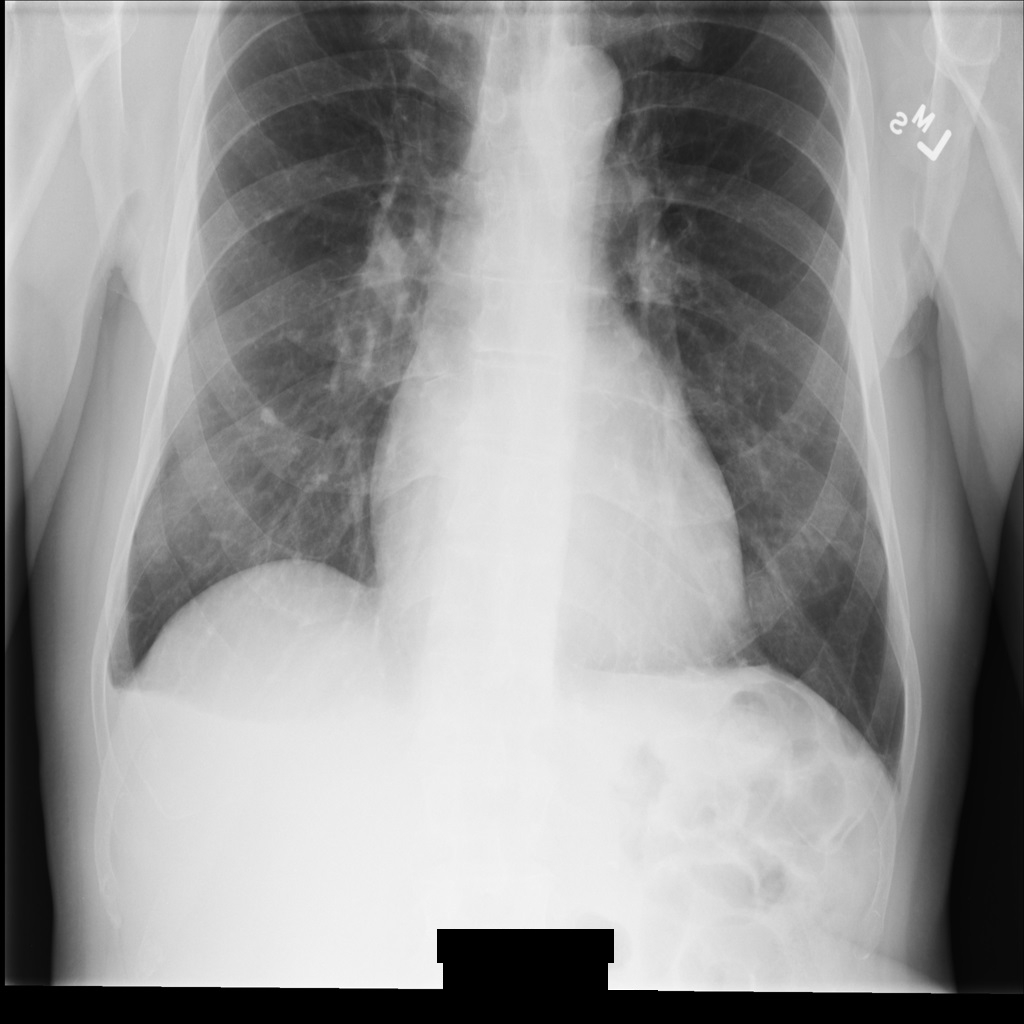

Beispielbild

Einige Beispiele auf dieser Seite enthalten eine Ausgabe des de-identifizierten Bildes. In jedem Beispiel wird das folgende Originalbild als Eingabe verwendet. Sie können das Ausgabebild jedes De-Identifizierungsvorgangs mit diesem Originalbild vergleichen, um die Auswirkungen des Vorgangs zu sehen:

Die meisten Beispiele auf dieser Seite enthalten eine Ausgabe der geänderten Metadaten in der DICOM-Instanz. In jedem Beispiel werden die folgenden Originalmetadaten als Eingabe verwendet. Sie können die Ausgabemetadaten jedes De-Identifizierungsvorgangs mit diesen Originalmetadaten vergleichen, um die Auswirkungen der De-Identifizierung zu sehen: